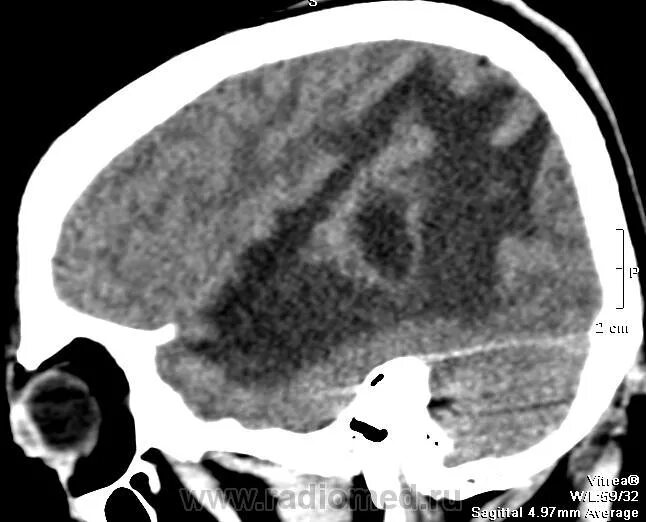

Метастазы в головном мозге мкб